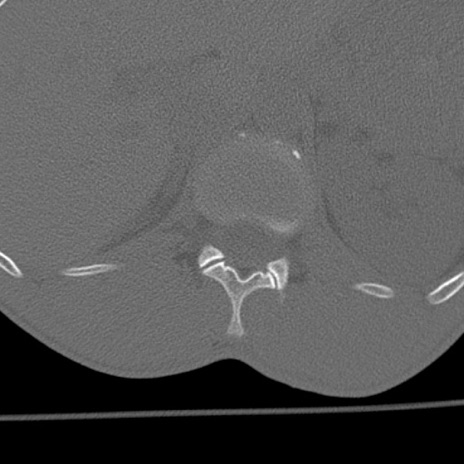

症例3 腰椎CT(横断像)

腰椎CT